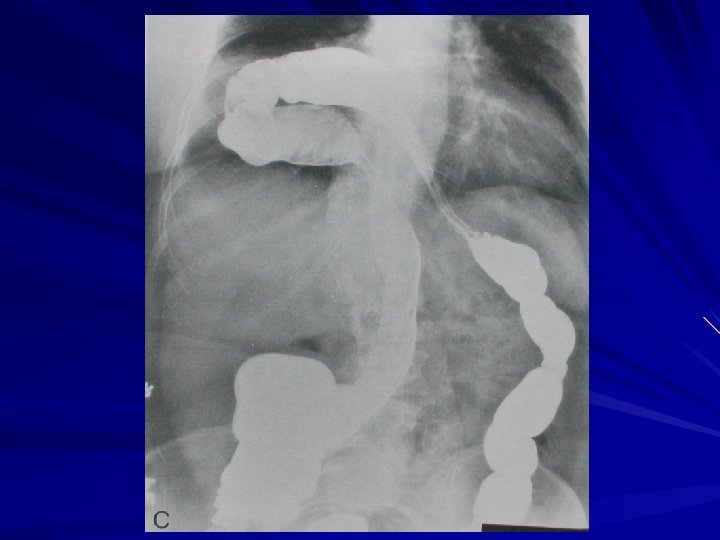

Arka mediasten kitleleri Nörojenik tm – paraspinal opasite, kemik erozyonu – kalsifikasyon (özellikle nöroblastomlarda) Özofagus lezyonları (hiatus hernisi, akalazya, tümör) Nörenterik kistler Ekstramedüller hematopoez Vertebral lezyonlar İnen aort anevrizmaları

Azigoözofageal reses Özefagus posterolateral kenarı ile vertebra anterior kenarının bileşkesinde bulunur, subkarinal alana uzanır Azigoözofageal resesin distal bölümünün sağa yer değiştirmesi (hiyatus hernisi olgusu)